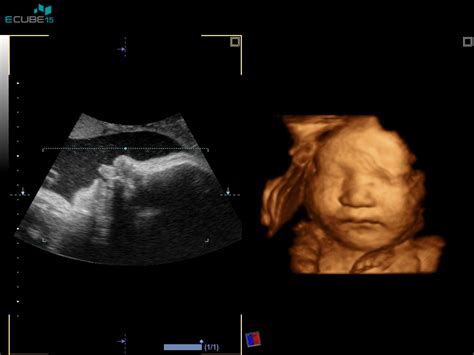

Temeljni kamen za zanesljivo oceno tveganja za kromosomske nepravilnosti predstavlja ultrazvočni pregled med 11. in 14. tednom nosečnosti. Že v tem zgodnjem obdobju lahko natančno pregledamo plod in odkrijemo določene strukturne nepravilnosti. Med ključnimi meritvami je določitev dolžine ploda od temena do trtice (CRL - Crown-Rump Length), kar omogoča natančnejše določanje termina poroda.

Najpomembnejši parameter za oceno tveganja za kromosomske nepravilnosti v tem obdobju je meritev nuhalne svetline (NT - Nuchal Translucency). Nuhalna svetlina predstavlja kopičenje tekočine v podkožju vratu ploda. Velja pravilo, da večja kot je izmerjena nuhalna svetlina, večje je statistično tveganje za prisotnost kromosomskih nepravilnosti, kot so trisomija 21 (Downov sindrom), trisomija 18 (Edwardov sindrom) in trisomija 13 (Patauov sindrom). Meritev nuhalne svetline se opravi med 11.0/7 in 13.6/7 tednom nosečnosti.

Dr. Pelkičeva in njeni sodelavci so tudi avtorji raziskav o uporabnosti tridimenzionalne (3D) ultrazvočne preiskave v porodništvu, vključno s pregledom plodovih možganov in srca. Te sodobne tehnike omogočajo še natančnejši vpogled v anatomijo in tudi motorične lastnosti ploda že v zgodnji nosečnosti. Pregled pri dr. Pelkičevi je pogosto opisan kot prijazen, korekten, kjer zdravnica vse razloži, pokaže ključne dele ploda in izda podroben izvid za ginekologa. Nekateri omenjajo tudi možnost snemanja pregleda na DVD, kar zahteva priložen DVD-R medij.